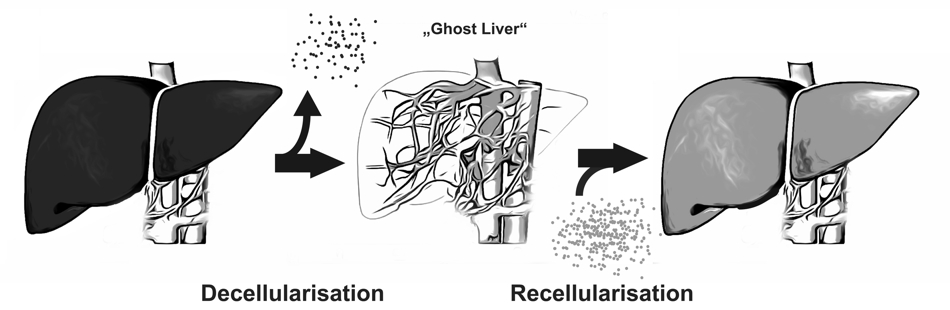

A new approach to overcome organ scarcity by in vitro generation of organoids is decellularisation and recellularisation of tissues or whole organs. This concept is based on the idea of composing biologic scaffolds by removing cellular and antigen-presenting components from tissues or organs, obtaining the organs’ extracellular matrix

A new approach to overcome organ scarcity by in vitro generation of organoids is decellularisation and recellularisation of tissues or whole organs. This concept is based on the idea of composing biologic scaffolds by removing cellular and antigen-presenting components from tissues or organs, obtaining the organs’ extracellular matrix (ECM).

The ECM represents the secreted products of resident cells and preserves the complex architecture and three-dimensional structure of the organ and thus generates a biomatrix ideally suited for reseeding with cells. This implies several advantages compared to other bioengineering concepts:

By preserving the organ’s ultrastructure, including the vascular network, oxygen and nutrient transport to the cells is warranted.

The ECM interacts with the reseeded cells and can act as a proliferation and differentiation inductive template for (autologous) stem cells or progenitor cells.

With this technique, scaffolds from marginal organs e.g. from non-heart beating donors or xenogeneic origin could be used for recellularization with the patient’s own cells. In this manner organ shortage could be overcome and post-transplant lifelong immunosuppressive therapy regimens would be dispensable. Another interesting potential application for these in vitro engineered organoids is their usage in pre-clinical drug discovery or toxicology or as a model for divers liver diseases (i.e. viral infections, hereditary metabolic diseases).

Recent reports on liver de- and recellularization provide evidence that the perfusion of alkaline detergents and/or enzymatic solutions via the portal vein is feasible to obtain a three-dimensional non-immunogenic biomatrix, that supports and improves survival and functionality of liver and/or progenitor cells. To enhance engraftment, migration and proliferation as well as to prevent dedifferentiation and loss of function of hepatocytes used for the repopulation of decellularized scaffolds, an adequate composition of micro-environmental conditions of the ECM is essential.